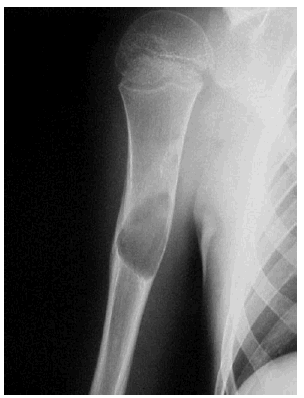

- Estructura: se deben seguir los contornos del hueso y comentar cualquier anomalía por ejemplo, fractura, callo y exostosis (crecimiento óseo). Figuras 4-6